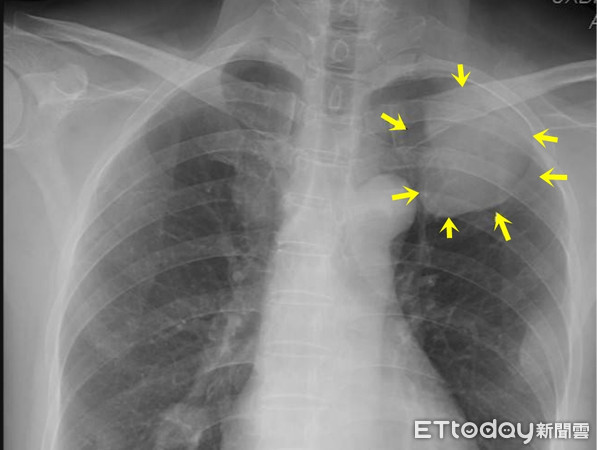

根據《TVBS新聞網》報導,這名病患在母親因肺癌離世後,心生警惕前往醫院檢查,結果真的發現罹患肺癌,但所幸是初期,立即進行手術處理。不料,他想起弟弟最近有持續咳嗽的症狀,便建議他也去檢查,沒想到X光檢查出現異常,進一步安排電腦斷層檢查後,竟然已經是第四期肺癌,甚至已經出現轉移的情況。